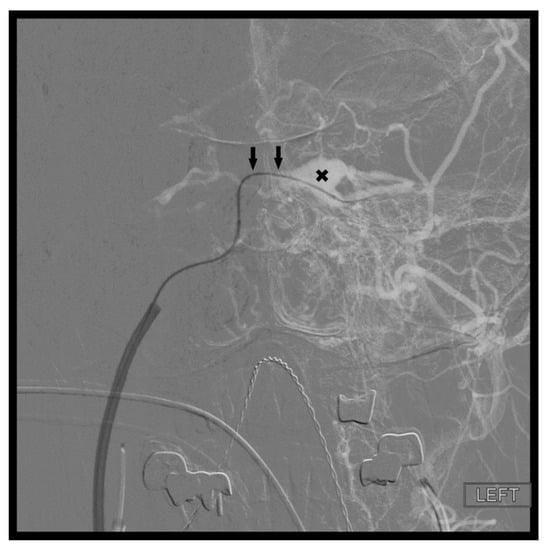

Figure 7. Demonstrates percutaneous transorbital puncture of the cavernous sinus (X) via the inferior ophthalmic vein (arrow).

9. Percutaneous Transorbital Puncture of the Cavernous Sinus, Inferior Ophthalmic Vein, or Superior Ophthalmic Vein

When transfemoral access to the fistula site is not possible, direct percutaneous transorbital puncture of the CS, SOV, or IOV can be an effective alternative. Kurata et al. described direct percutaneous puncture of the extraconal portion of the SOV in three patients with traumatic CCFs in which transarterial and IPS approaches failed [18]. In their approach, the extraconal portion of the SOV is cannulated with an 18-gauge sheathed needle inserted into the upper portion of the medial orbital angle. The needle is guided by transfemoral angiographic roadmapping technique. The anterior apsidal vein located between the first and second segments (intraconal portion) of the SOV is used as a landmark. More commonly reported is direct puncture of the IOV. The IOV begins as a network of veins along the anterior/medial wall of the orbit. The IOV runs posteriorly along the lower half of the orbit, above the inferior rectus muscle, until it divides into two branches. The inferior branch passes through the inferior orbital fissure and contributes to the pterygoid plexus. The superior branch passes through the superior orbital fissure (SOF) and either enters the anterior CS directly or, more commonly, joins the SOV before draining into the CS. White et al. described their series of eight patients with CCFs treated by direct transorbital puncture of the IOV or CS and subsequent coil embolization [19]. All eight patients experienced complete obliteration of their CCF in a single procedure, and there were no permanent periprocedural complications. In this approach, transfemoral access is first obtained to investigate the fistula as well as to provide transarterial diagnostic angiograms. Once it is discovered that the traditional venous pathways are not accessible, the ipsilateral orbit is prepped and draped in the usual sterile fashion. A 21-gauge needle and a 4 French micropuncture kit are used for percutaneous access. The 21-gauge spinal needle, attached to aspiration tubing, is inserted into the inferolateral aspect of the orbit and gradually advanced along the orbital floor. Under live fluoroscopic guidance, the tip of the needle is directed towards the superior orbital fissure (SOF). The SOF is separated from the optic canal by placing the AP tube in an oblique 45-degree projection, while keeping the floor of the orbit flat. Care is taken to not damage the optic nerve within the optic canal. While the needle is advanced, gentle aspiration is applied to the tubing with a 5 mL syringe until venous return is obtained. The tubing is then removed, and the micropuncture wire (0.018 gauge) is inserted through the needle. Next, the needle is exchanged for a 4 French introducer sheath (alternatively the needle can be left in place and direct injections through the needle can be performed). A venogram is performed through the sheath to confirm positioning within the IOV or the CS itself. Care must be taken to perform only gentle injections in these settings to avoid applying increased pressure in what is already an over pressurized system as this can lead to vessel rupture and significant morbidity. Next, using roadmapping technique a microcatheter is advanced coaxially over a microwire into the CS (Figure 7). Once the embolization is complete, a diagnostic angiogram is performed through the arterial catheter to confirm resolution of the fistula. The microcatheter and sheath are then removed, and gentle pressure is applied to the puncture site. A dressing is generally not necessary. This approach is particularly useful in fistulas located within the anterior CS which have prominent drainage into the ophthalmic veins. Additionally, the direct percutaneous access to the CS avoids the need for surgical exposure of the ophthalmic veins. It is important to note, however, that perforation of an orbital vein carries higher consequences than perforation of a facial (angular) vein. Therefore, this approach should be reserved for patient′s in which lower risk approaches are not possible. It is recommended that ophthalmology be available for emergent optic nerve and/or globe decompression if necessary.